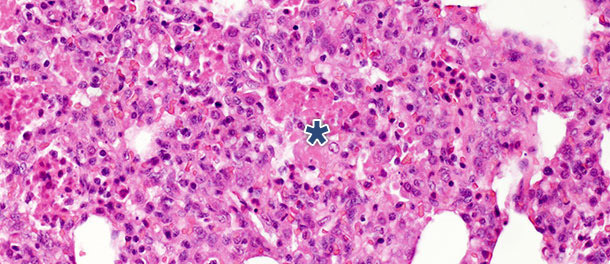

Dans une étude avec challenge dans laquelle on a euthanasié les porcs à 14 et 21 jours PI, on a observé chez les animaux infectés une diminution significative des débris nécrotiques intra-alvéolaires et des cellules inflammatoires à 21 jours PI. En revanche, on a observé un léger changement dans les trois autres catégories. Ces découvertes peuvent être expliquées par le fait que la formation des débris nécrotiques intra-alvéolaires et par conséquent l’accumulation intra-alvéolaire des cellules inflammatoires (essentiellement granulocytes neutrophiles) reflètent la phase aigüe de la maladie (photo 2) dans lesquelles les substances nocives libérées par les macrophages infectés entraînent une importante atteinte tissulaire. Après la phase initiale et aigue, en l’absence d’infection bactérienne secondaire, le système immunitaire et les mécanismes naturels de guérison éliminent le tissu nécrotique, c’est pourquoi les cellules de l’inflammation aigue (granulocytes neutrophiles) disparaissent, les alvéoles se vident et les pneumocytes endommagés sont remplacés par des pneumocytes prolifératifs de type II.

Photo 2 : débris nécrotiques intra-alvéolaires et accumulation de cellules inflammatoires (astérisque) dans le tissu pulmonaire à 10 jours après PI avec un isolat du virus du SDRP de type 1 sous-type 1 H. E. 200 x.